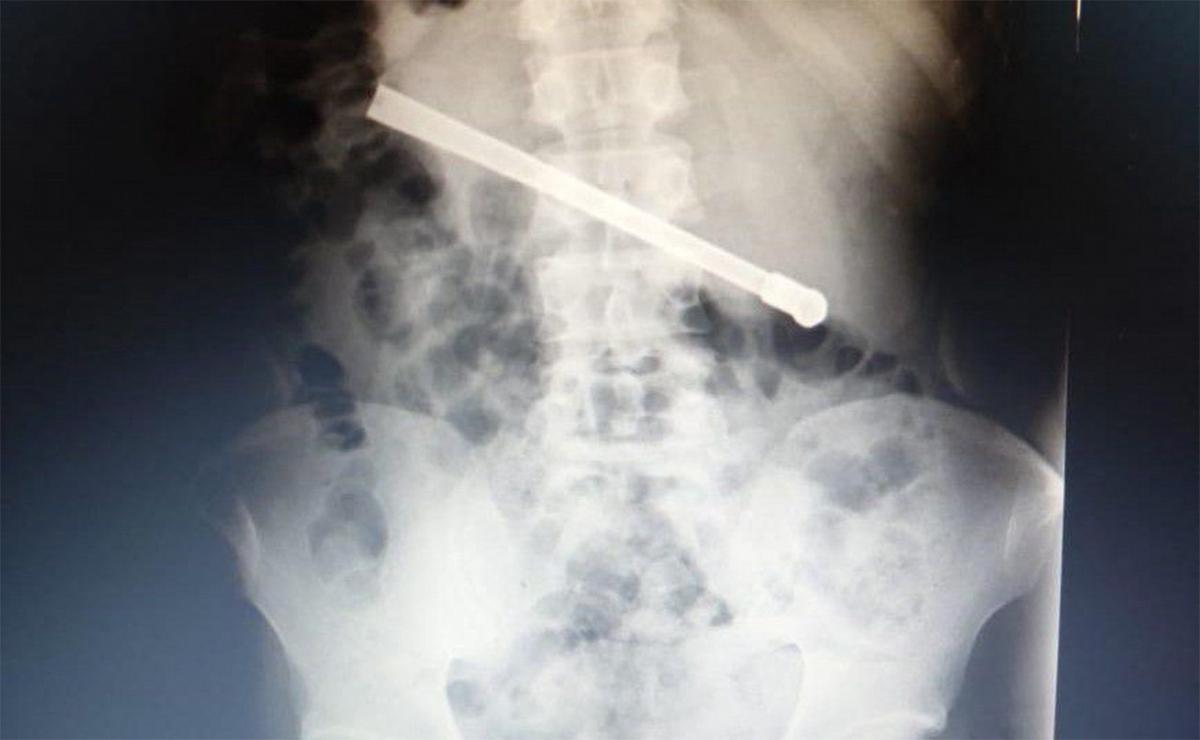

Un detenido del Complejo Penitenciario Rosario (CPR) debió ser trasladado de urgencia al hospital Eva Perón luego de que los médicos descubrieran que había ingerido una bombilla de mate, la cual quedó alojada en su cavidad torácica. El hecho ocurrió en la noche del domingo, cuando el interno, de 35 años, comenzó a sufrir fuertes dolores estomacales y requirió atención médica inmediata.

Tras ser evaluado en el servicio médico de la unidad penitenciaria, ubicada en 27 de Febrero al 7800, se le realizó una placa radiográfica que reveló la presencia del objeto metálico atravesado en el tórax

Ante la gravedad del caso, las autoridades penitenciarias dispusieron su traslado al hospital Eva Perón, donde fue sometido a una cirugía de urgencia en la tarde de este lunes. La intervención fue exitosa y los médicos lograron extraer la bombilla. El hombre permanece en observación y, una vez estabilizado, será reintegrado al CPR.